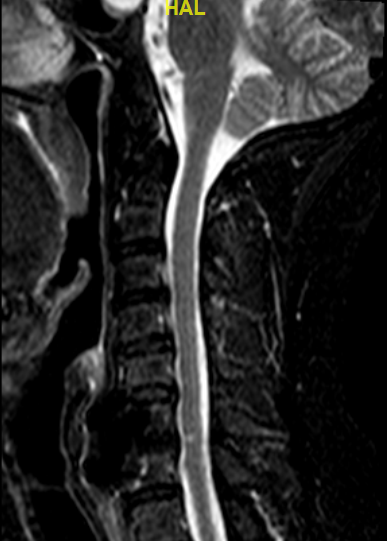

RM postoperatoria 1 año

Obsérvese la altura del espacio C6-C7 incrementada con la caja atornillada